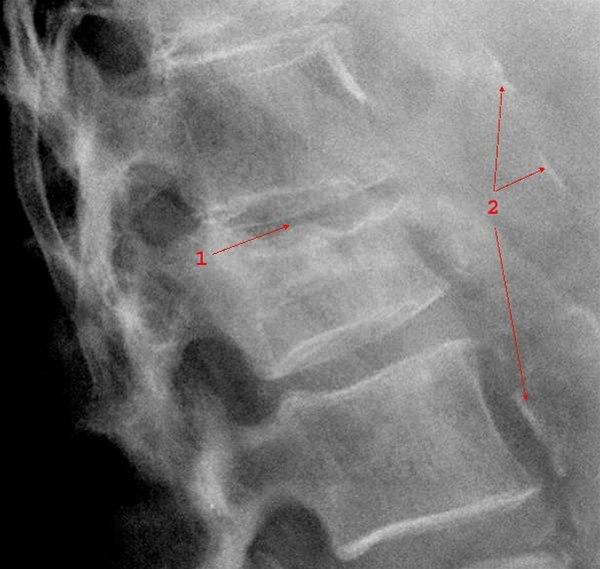

- Kompresjonsbrudd

- Betyr at selve virvelen er blitt presset sammen i lengderetningen (se illustrasjonene over). En bruddtype som er vanlig ved beinskjørhet, og som vanligvis er et stabilt brudd.

Røntgen kan avklare diagnosen. Ved mistanke om instabilitet og ved nakkeskader tas CT. MR tas kun ved behov for bedre bilder av ryggmargen og leddbånd.

Målet med behandlingen er å forebygge komplikasjoner og varige nevrologiske skader ved ustabile brudd. Ved stabile brudd er målet å gi symptomlindring. Stabile skader behandles konservativt, mens ustabile vurderes operert.

Ustabile skader overveies operert. Man vil da forsøke å stabilisere bruddet. Det gjøres oftest ved å "skrue sammen" ryggvirvler over og under bruddstedet. Andre ganger fjernes beinvev som kan trykke på ryggmargen (dekompresjon). I noen tilfeller må man fjerne eller sette på plass beinstykker som har forskjøvet seg inn i ryggmargskanalen. Som regel må slike inngrep gjøres på et universitetssykehus.